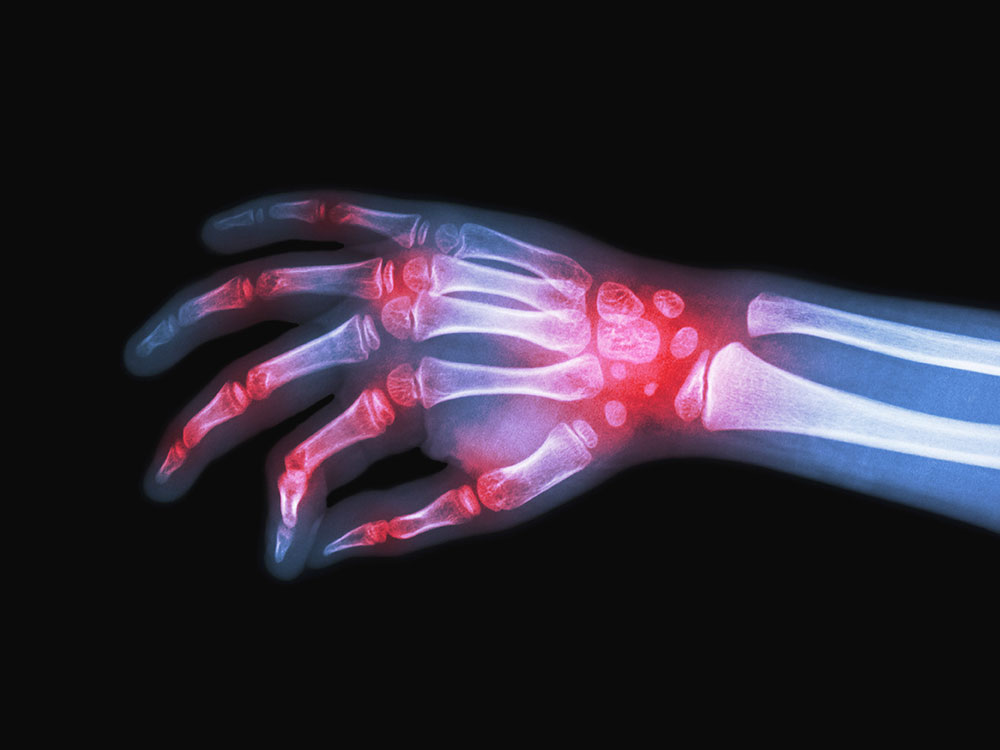

As doenças reumáticas acometem o aparelho locomotor, ou seja, ossos, articulações, cartilagens, músculos, tendões e ligamentos. Algumas também podem comprometer outras partes do corpo humano como rins, coração, pulmão, pele, sistema circulatório, cérebro e o sistema nervoso central. Essas enfermidades reumáticas estão entre as principais causas de afastamentos do trabalho e podem levar a limitações físicas se não diagnosticadas e tratadas adequadamente. Entre os sintomas mais frequentes estão dores nas articulações, rigidez e inchaço, que podem, dependendo do estágio da doença, levar à deformidade nos pés e nas mãos, desgaste nas cartilagens e nos ossos.

A osteoartrite ou artrose, de acordo com a SBR, é a doença reumática mais frequente no país, representando cerca de 30% a 40% das consultas em ambulatórios de reumatologia. Já a artrite reumatoide, doença de natureza inflamatória, crônica e progressiva, acomete cerca de dois milhões de pessoas no Brasil. Trata-se de uma doença mais prevalente entre mulheres, na faixa dos 30 aos 55 anos, mas também atinge pessoas de todas as idades, inclusive crianças e adolescentes.

Com a preocupação de alertar e conscientizar a população, especialistas da Sociedade Brasileira de Reumatologia (SBR) estarão em contato direto com a população esclarecendo dúvidas em relação a doenças reumáticas como Artrite Reumatoide, Fibromialgia, Osteoporose, Osteoartrite/Artrose, Espondiloartrites, Artrite Psoriásica, Lombalgia, Lúpus Eritematoso Sistêmico (LES), Gota, Febre Reumática, Vasculites, Doença de Sjögren, Doença de Behçet, Esclerose Sistêmica (ES) e outras. Cada doença tem sua característica. A artrite reumatoide, por exemplo, é uma doença crônica e ocorre quando há uma alteração do sistema imunológico, que ataca as articulações.

De acordo com o especialista, o diagnóstico e o tratamento nas fases iniciais das doenças reumatológicas são muito importantes para que o paciente consiga ter uma vida produtiva e de qualidade. “Dores nas articulações podem ser sintomas de doenças reumáticas, como artrite e osteoartrite/artrose, e devem ser investigadas, diagnosticadas e tratadas de forma adequada por um reumatologista”, ressalta.